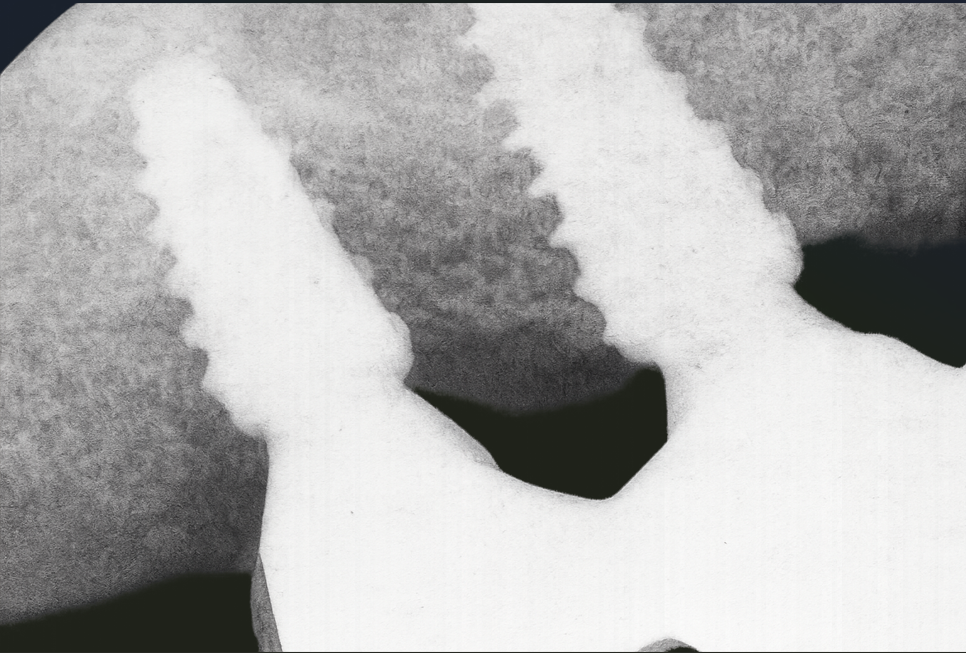

그럼 사진처럼 치조골이 회복되어 임플란트를 치조골이 안정적으로 감싸게 되죠.

임플란트 주변 뼈조직을 확대해서 촬영한 사진을 발산동 치과 에서 준비해 봤습니다. 진한 부분이 새로 형성된 뼈고, 밝은 부분이 기존 골조직이거나 이식 재료인데, 연구를 통해 PDRN을 사용한 경우, 새로 형성된 뼈가 많아 골 유착이 더욱 원활했다는 결과를 확인할 수 있었습니다. *Park JH 외 2022 J periodontoal lmplant sci